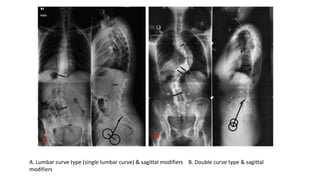

Modified Lenke's criteria for defining fusion. (A&B): Examples of ...